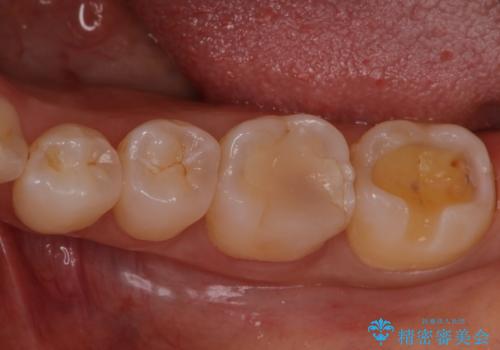

銀歯を無くしたい セラミックインレー

- 銀歯が気になるということで来院された患者様です。

セラミックでの治療を希望されたので治療をいたしました。

銀歯は長い間使用していると隙間ができて、虫歯の原因になります。

そのため適合の良いセラミックをお勧めいたします。